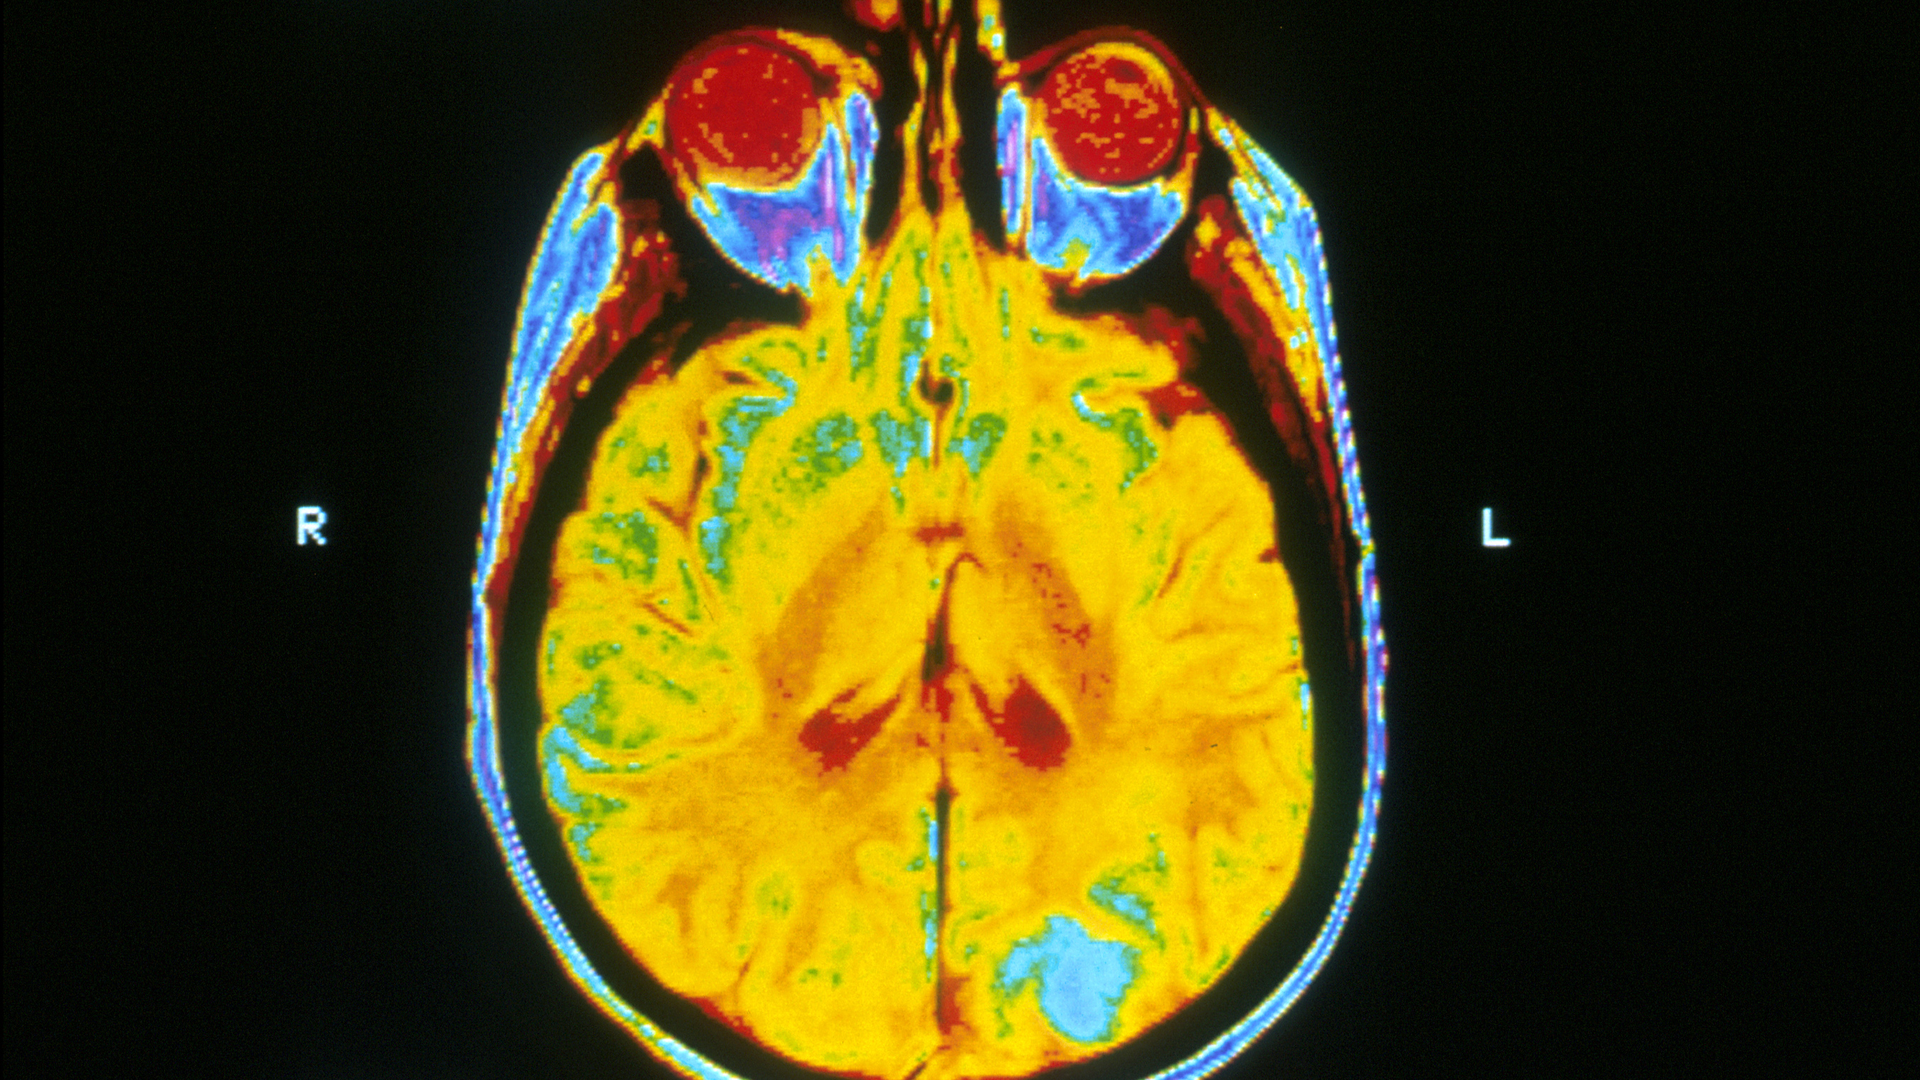

Image: ‘Brain MRI’ (public domain), source: https://commons.wikimedia.org/wiki/File:Brain_MRI.jpg. Changes: cropped and resized to 1920×1080.